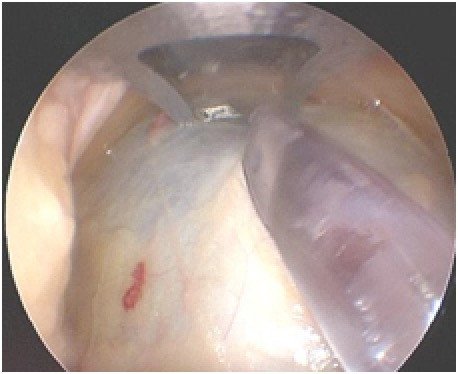

Bei der Operation werden über zwei kleine Inzisionen direkt über den betreffenden Muskellogen am Unterschenkel kniegelenksnah eine Kamera sowie eine Spezialklinge eingeführt, um die gespannte Abgrenzung der Loge, die Unterschenkelfaszie, nahezu in ihrer gesamten Länge unter Sicht zu spalten.